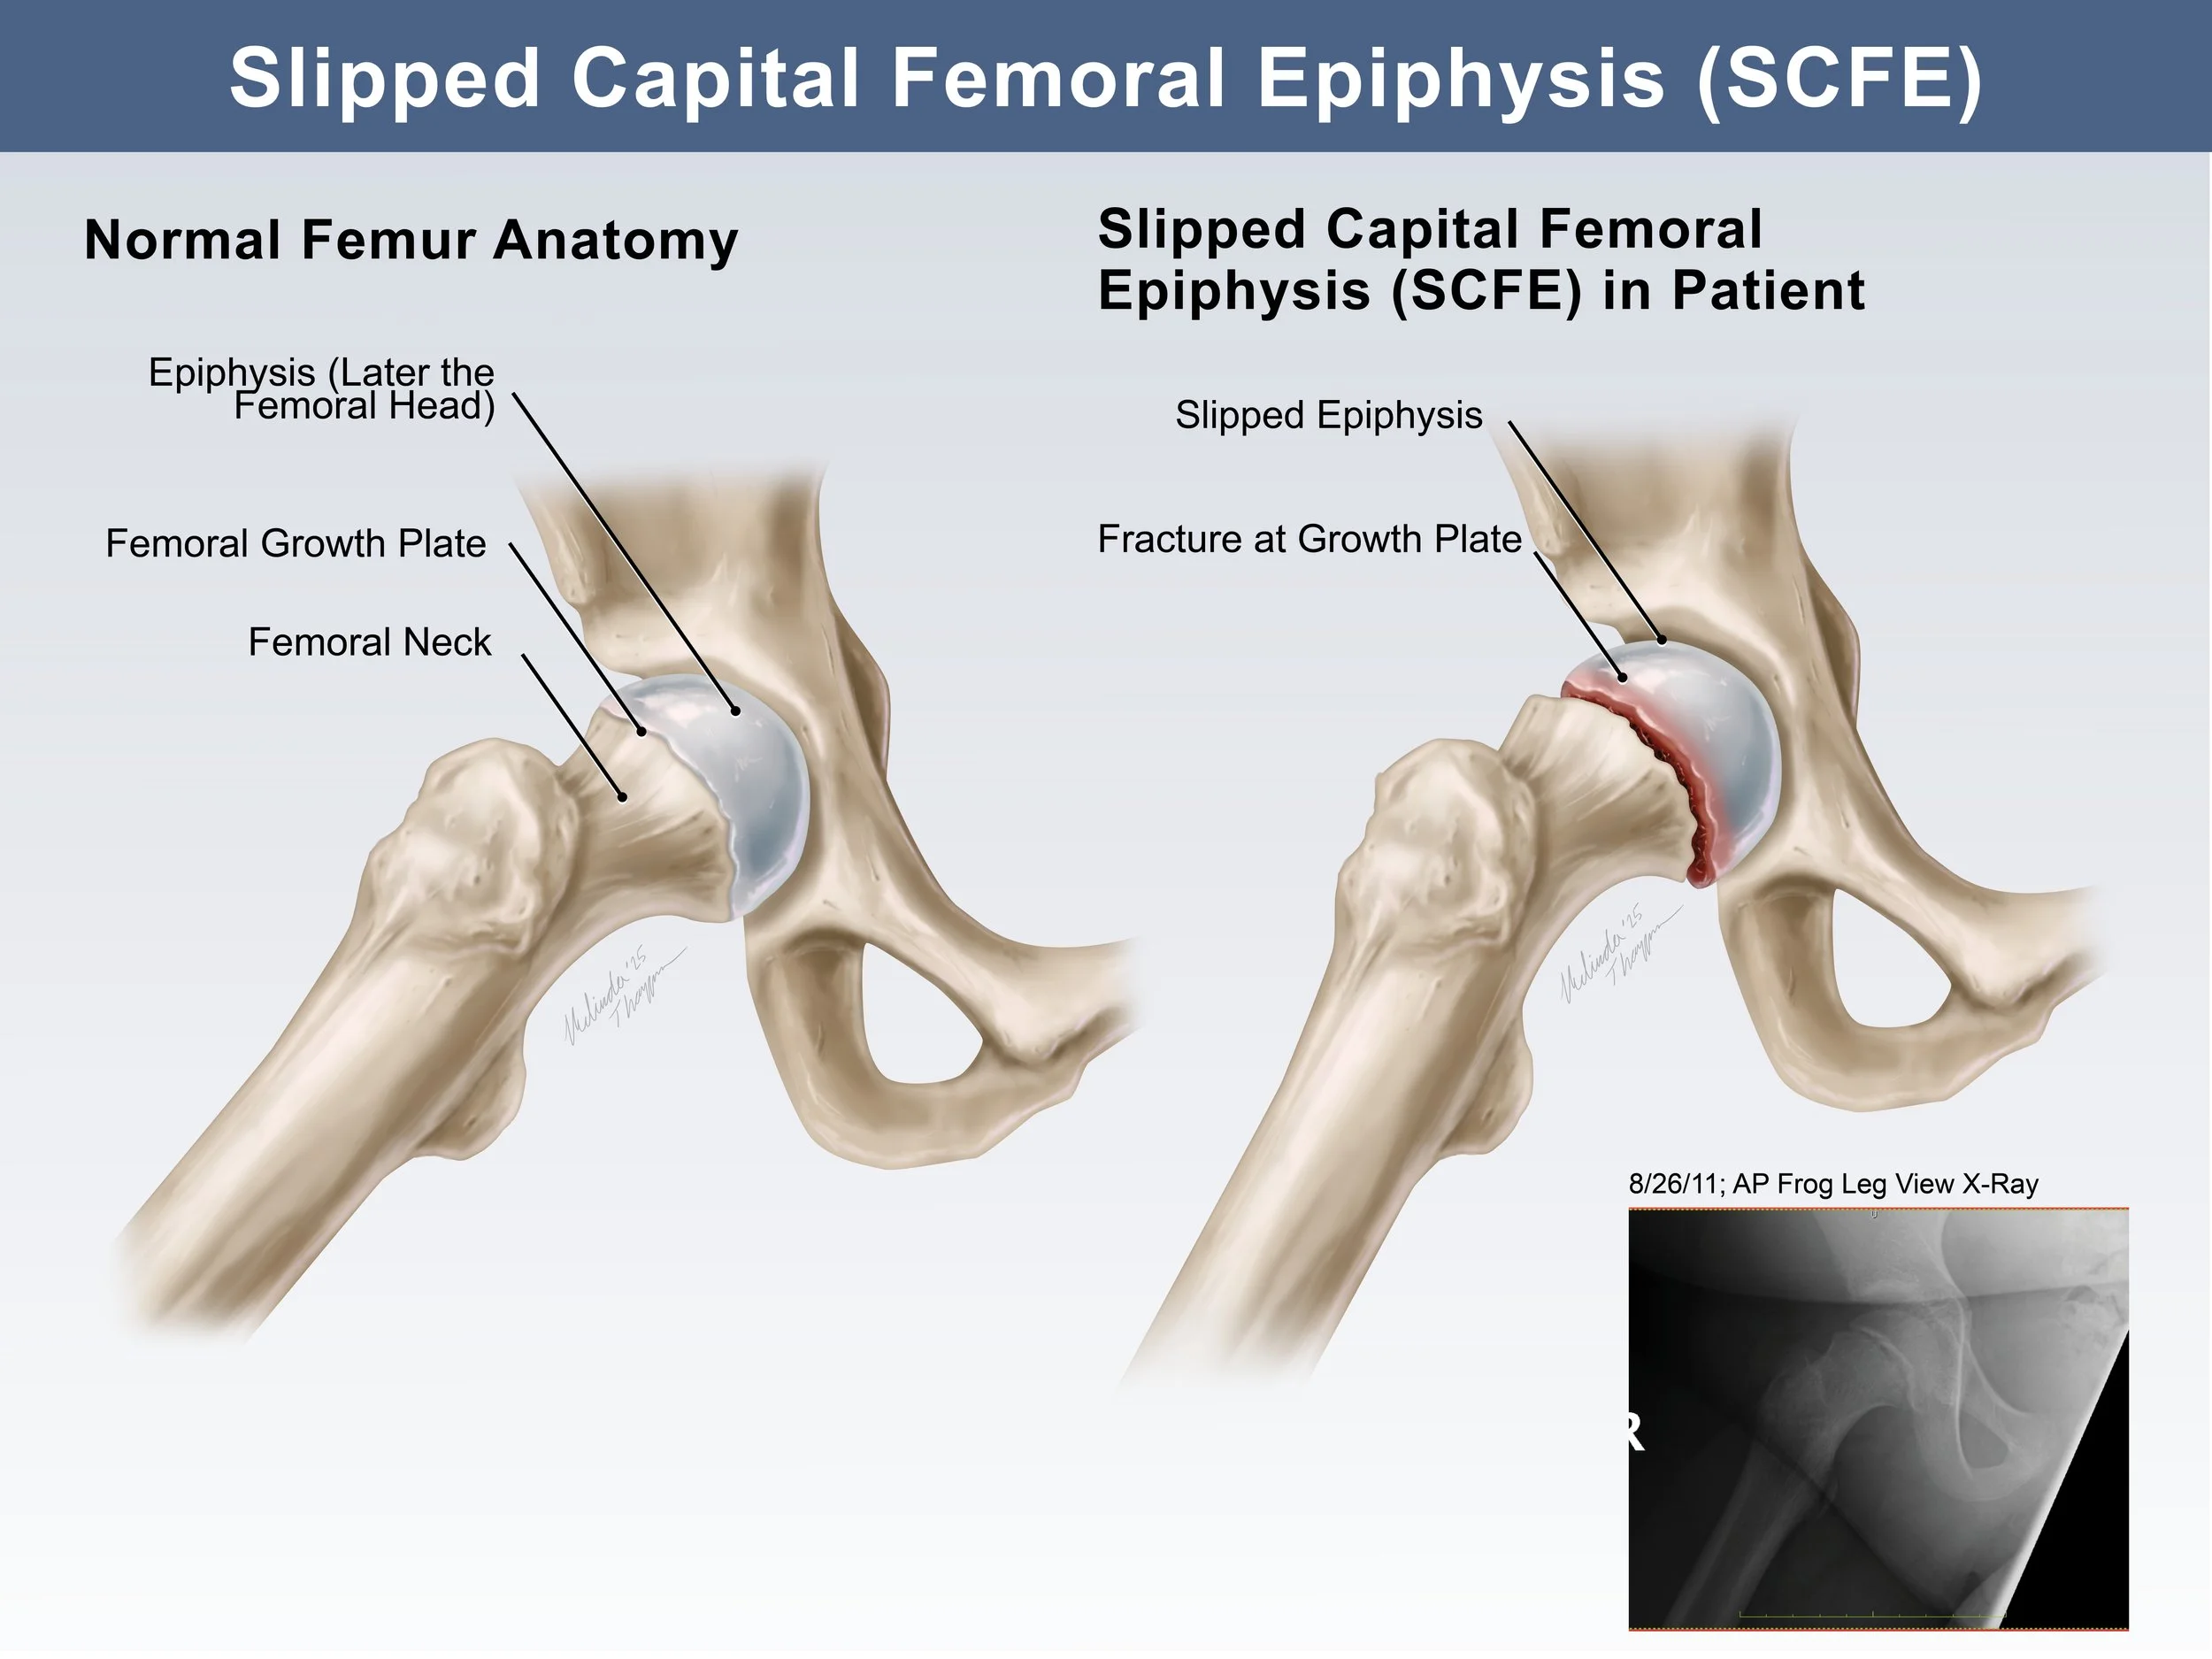

Medical Legal Illustration

Medical Illustration is important in the courtroom for many reasons including communicating scientific information for a lay audience, highlighting injury or anatomical differences, or simply representing potentially disturbing images in a more digestible way. Legal illustrations must be accurate, but still serve to help tell the defendant or plaintiff’s story.

SCFE Exhibit Design

These illustrated slides were created for a medical legal illustration course to accompany the plaintiff’s case in a “mock trial” presentation. The illustrations show the the progress of a slipped capital femoral epiphysis fracture (SCFE) that ultimately led to disability in a young girl. The illustrations were used to clearly communicate x-ray information to a lay audience and demonstrate why the doctor’s misread was easily avoidable. Additionally, the illustrations show the progression of symptoms as a result of that first missed diagnosis.

Adobe Photoshop, Indesign